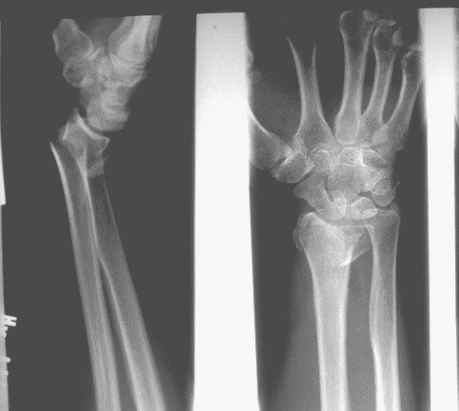

Case 2 Preop